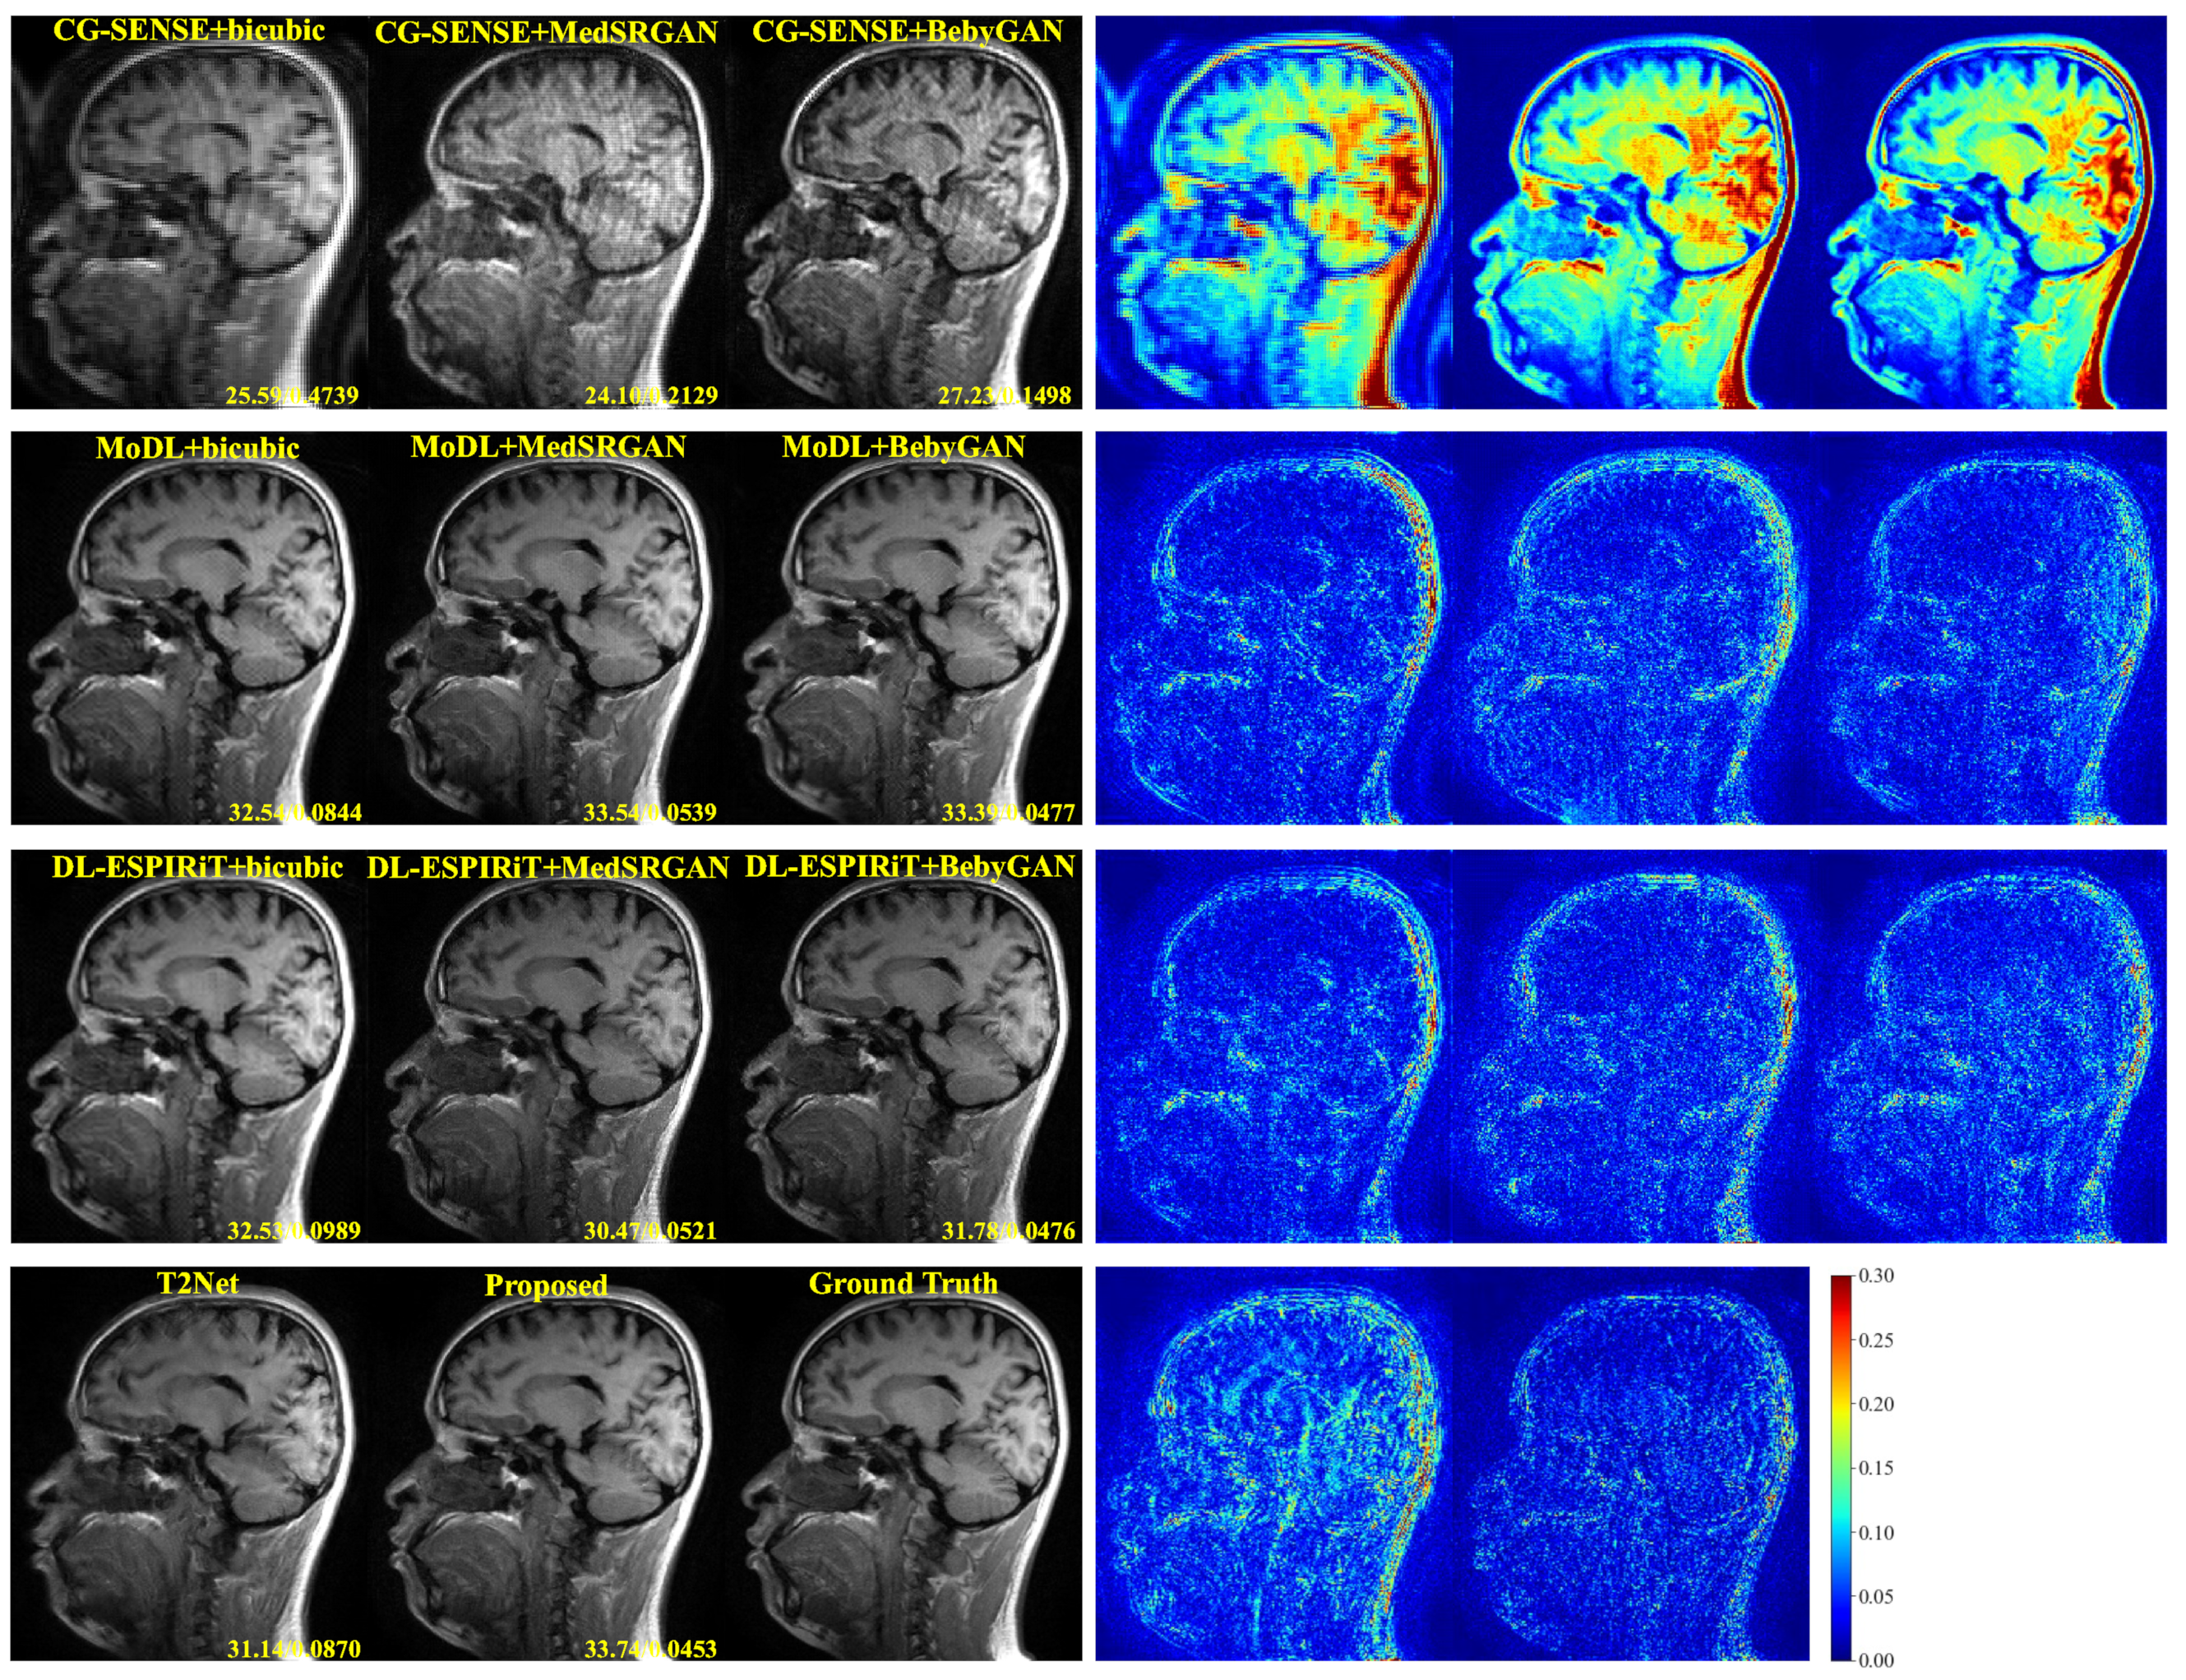

For a more intuitive comparison, we provide visual comparisons for each method. In Figure 5 and Figure 6, we illustrate the axial and sagittal views of the 2D brain dataset, respectively. In Figure 7 and Figure 8, we display the brain image and neck image of the 3D VWI dataset. For each method, we show the restorations along with the corresponding error maps. The images are placed on the left, the error maps on the right, and the PSNR and LPIPS metrics of each image are shown at the bottom right corner. From the error maps, it is evident that our proposed method consistently produces high-quality results with improved visual fidelity and better retention of structural information compared to the other methods.

Figure 6. Visual comparison of each method for a slice of sagittal view in the brain dataset.

Bioengineering 10 01107 g006